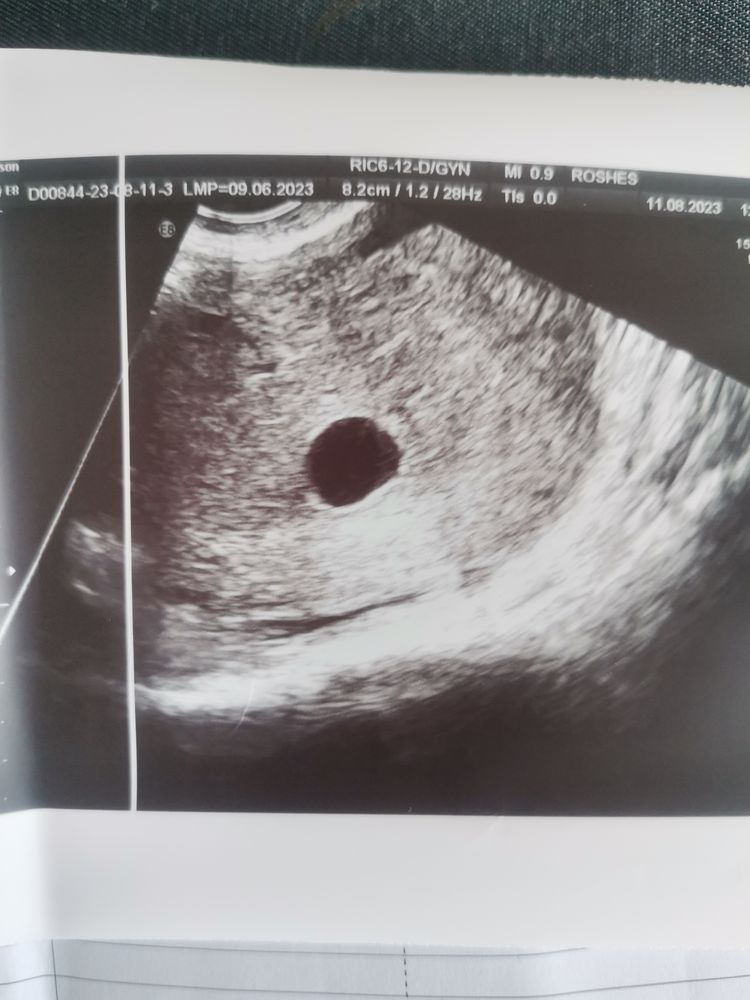

Снимок к предыдущему посту

Прикладываю снимок к последнему посту, 9 акушерских недель, пя 13 мм пустое.. Больше не хочу себя тешить надеждами , но это нормально, что там какие то белые тени, или это нормально, аппарат так размазывает? В понедельник пойду сдаваться😭😭😭😭

Если это непраздный О и динамики в узи нет, то это неразвивающаяся Б((( в 9 недель пя уже больше 3 см и эмбриончик большой! Удачи вам!

Евгения, поздняя овуляция, но к сожелению неделю назад пя было 10 мм(

У меня в 6 недель было пустоя пя 14 мм, через две недели всё появилось. Но пя должно расти по 1 см в день, поэтому тут без вариантов